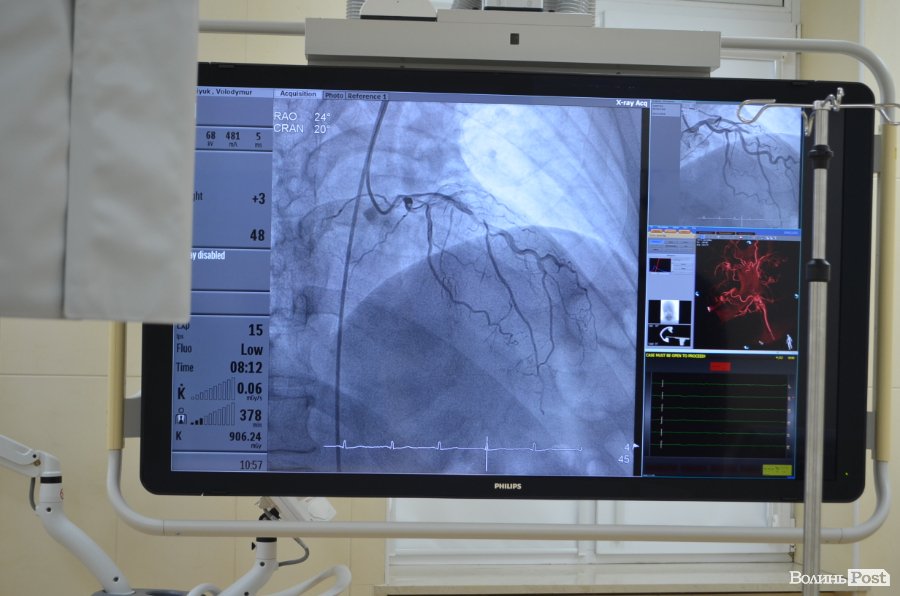

Ангіографічна система Philips Allura Xper FD20 – це одна із закупівель у рамках реалізації у краї субпроекту Світового банку «Вдосконалення медичної допомоги хворим з хворобами системи кровообігу у Волинській області». Її вартість – 619 259 доларів США.

Ця ангіографічна система експертного класу дозволяє проводити широкий спектр втручань на серці та судинах. Вона допомагає отримувати зображення з високою роздільною здатністю, має додаткові можливості для спеціальних процедур, а також може використовуватися в гібридних операційних.

«Це ангіограф, який має досить високу роздільну здатність, ми можемо побачити найдрібніші судини, аби визначити, чи є там патологія. Сам ангіограф є мультифункціональним, тобто він дозволяє обстежувати судини будь-якого людського організму. Це може стосуватися судин головного мозку, серця, нирок, печінки, верхніх та нижніх кінцівок. Ми можемо діагностувати судинні ураження, які відбуваються у певних органах і проводити оперативні втручання», — розповів Юрій Легкодух.

Також тут є 3D станція. Ми можемо побачити судини у 3D об'ємі. Це зручно у тому плані, що коли, наприклад, є аневризма головного мозку, яка може призводити до інсультів, за допомогою 3D реконструкції ми можемо точно, прицільно зайти катетером у судини головного мозку, саме в ту аневризму і запломбувати її. Так само відбувається реконструкція і інших судин»,— зауважив лікар.